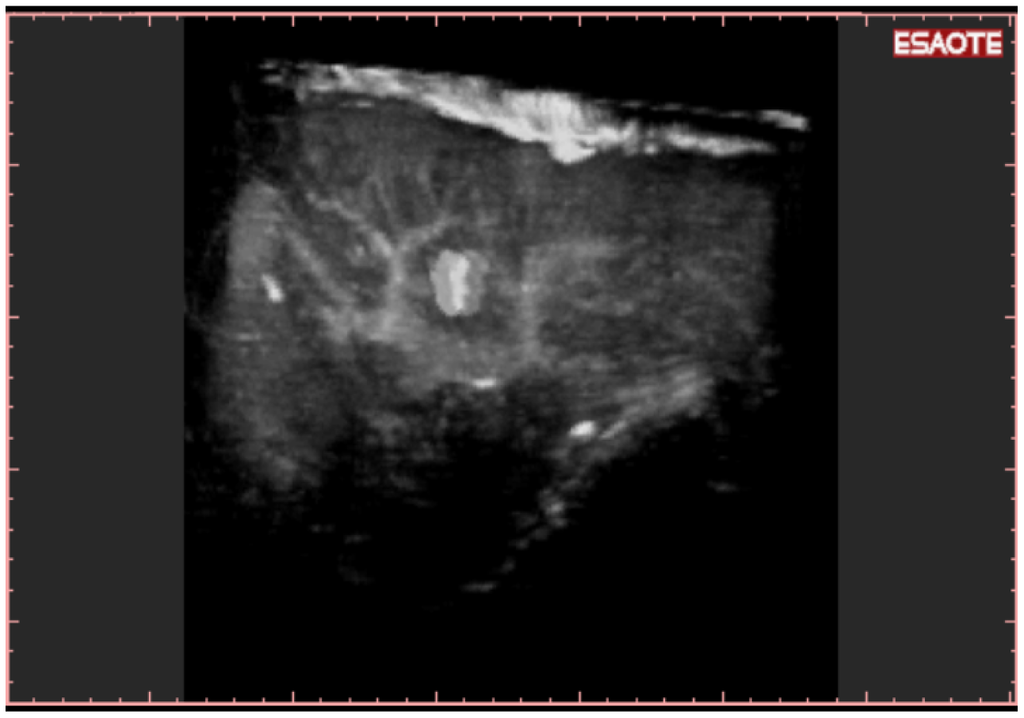

To easily perform a 3-D reconstruction of a 2-D acquisition of CEUS imaging of the whole liver, the 2-D acquisition is performed with real time scanning perpendicularly on the long-axis of the liver, for a complete 2-D image of its short-axis (Figure 2). The subsequent reconstructions of these planes show a rendered volume with a “parenchimal” aspect (Figure 5) or with a “vascular” map (Figure 6) of all the hepatic segments with an acquisition in the early arterial and in portal phase.

New US systems are able to perform 3-D reconstruction using contrast-agents imaging. This means that CEUS 3-D reconstruction is based on the macro and microcirculation. In this way, it enables detecting the enhanced vasculature of HCC during arterial phase and the typical late wash-out in the same manner as performed by spiral CT/MRI.